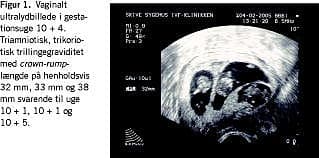

En vaginalskanning i uge 7+0 viste overraskende triamniotisk, trikoriotisk trillingegraviditet. Fostrene målte henholdsvis 8,4, 7,5 og 4 mm, svarende til gestationsuge 7+0, 6+5 og 6+1. Efterfølgende skanninger viste normal tilvækst, og parret afstod fra fosterreduktion (Figur 1).